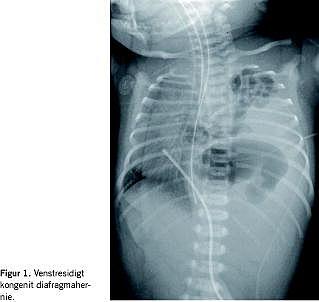

Kongenit diafragmahernie (CDH) forekommer med en hyppighed på 1:2.000-4.000 fødsler og med en overhyppighed på 1,5:1,0 hos drenge [1, 2]. CDH er en udviklingsanomali, der er karakteriseret ved en mangelfuld vækst og sammensmeltning af de anteriore og posteriore komponenter i diafragma, der sker i ottende gestationsuge. Defekten i diafragma resulterer i en herniering af mave-tarm-kanalen til lungehulen. Den venstresidige form udgør ca. 90% (Figur 1 ). Årsagen til misdannelsen er ukendt. Lidelsen ses i sjældne tilfælde som led i veldefinerede syndromer [1, 3].